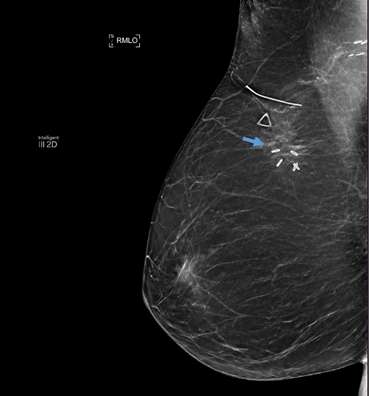

Mammographic Findings: On mammography, fat necrosis typically presents as a well-defined, round or oval mass with varying densities. Initially, it may appear as a radiolucent mass due to the liquefaction of necrotic fat. Chronic lesions may develop rim or “eggshell” calcifications; this appearance is benign when associated with history of trauma and does not require specific imaging follow-up or treatment. As fat necrosis evolves, fibrosis may develop in a spiculated or irregular morphology, which can present similarly on mammogram to breast carcinoma.3 In these cases, correlation with clinical history, close follow-up and/or biopsy may be necessary to distinguish benign fat necrosis from malignant breast masses.